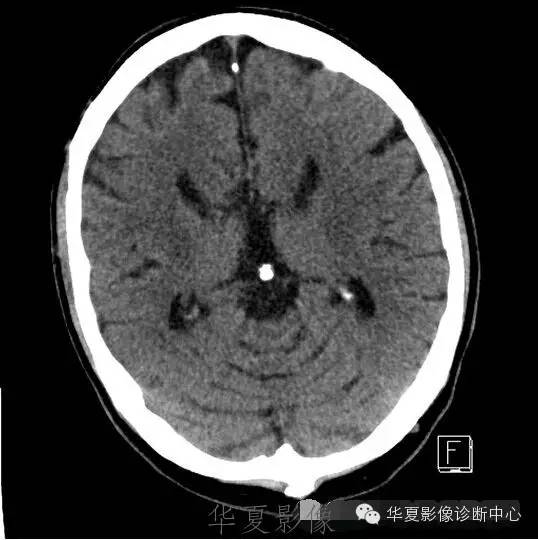

8种颅脑先天畸形ct诊断

图片尺寸538x540

脑裂畸形伴透明隔缺如

图片尺寸512x512

看图说话1脑灰质异位脑裂畸形

图片尺寸1417x1518

先天性脑裂畸形

图片尺寸600x600

原创共享典型小儿颅脑先天畸形脑裂畸形

图片尺寸864x864